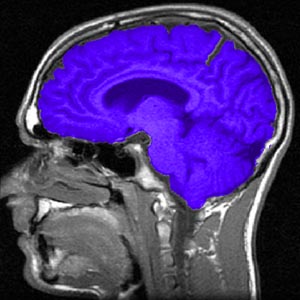

Neurofisiologia